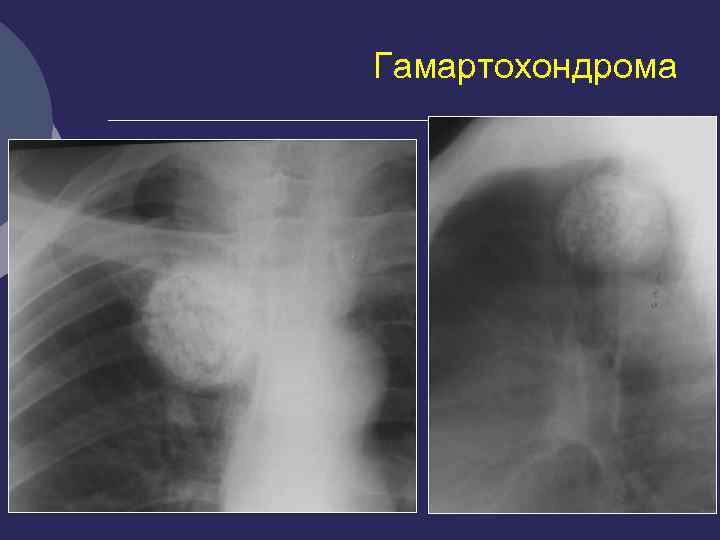

Гамартохондрома Ø Нарушение развития мезо- и энтодермы Ø Макроскопически – образование шаровидной формы, эластической консистенции, с мелкобугристой поверхностью (дольчатое строение) Ø Капсула отсутствует, есть ложе Ø Микроскопически: между хрящевыми элементами включения миксоидной, волокнистой соединительной, мышечной, жировой, сосудистой ткани

Гамартохондрома В отличие от туберкуломы – Ø значительно чаще находится в правом легком (почти в 2/3 случаев) Ø преимущественно (у 75% больных) в 3 -м, 4 -м, 5 -м, 7 - м и 8 -м сегментах легкого Ø Располагается - в периферических отделах и вблизи корней легких, иногда субплеврально, по ходу междолевой плевры

Ретгенологические признаки гамартохондромы Ø Правильная форма Ø Четкие гладкие или волнистые контуры Ø Средняя интенсивность Ø Включения извести (глыбки, слоистость, инкрустации) Ø Окружающая легочная ткань не изменена Ø Бронхи, сосуды огибают образование

Гамартохондрома